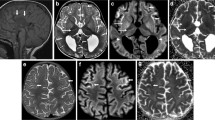

Cranial MRI findings were diffuse hypomyelination in 80 % (n: 8/10), corpus callosum dysgenesis in 60 % (n: 6/10), ventricular dilatation in10 % (n: 1/10), hydrocephalus in 10 % (n: 1/10), and mega cisterna magna in 10 % (n: 1/10). Two of the four patients who underwent cranial MRS had a glycine peak (patient no: 2 and 4) but MRS was normal in two patients (patient no: 3 and 9), one of whom had normal plasma glycine level under treatment at the time of MRS acquisition (patient no: 3). EEG findings were multifocal epileptic activity in 100 % (n: 10/10), burst suppression pattern in 70 % (n: 7/10), hypsarrhythmia in 50 % (n: 5/10) and cerebral dysfunction in 20 % (n: 2/10).

Abnormal myelination, gyral malformation, progressive atrophy, parenchymal volume loss, corpus callosum dysgenesis and hydrocephalus on brain MRI have been reported in classic NKH (Van Hove et al. 2000; Roy et al. 2004; Mohammad and Abdelkhalek 2017; Shbarou et al. 2019; Stence et al. 2019). Lack of growth of the corpus callosum (shorter length and decreased thickness) was common, and this growth failure was found directly related to the severity of the clinical phenotype (Stence et al. 2019). Diffuse hypomyelination, corpus callosum dysgenesis and rarely hydrocephalus were observed in our patients, similar to the literature. Increased glycine peak in cranial MRS is typical and useful in the diagnosis and monitoring of treatment in NKH have been reported (Shin et al. 2012; Stence et al. 2019). Severe patients were found to have the greatest glycine/creatine ratios (Stence et al. 2019). In our study two patients had a glycine peak but normal in two patients whom one of under therapy. Treatment might decrease the glycine peak in the brain MRS parallel to the decrease in plasma and CSF glycine levels in this patient. Therefore, since lumbar puncture (L/P) is an invasive procedure, brain MRS can be used instead of lumbar puncture in diagnosis and monitoring of treatment in classic NKH.